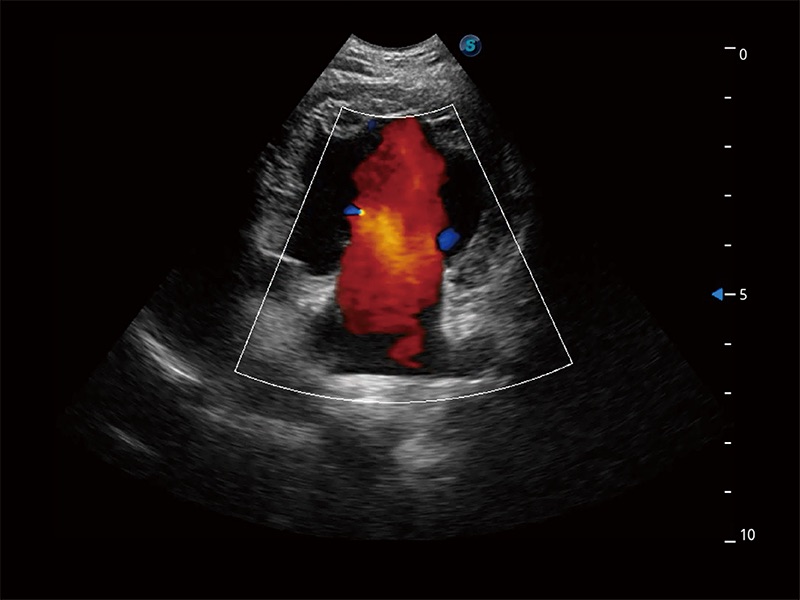

ProPet 80 配备了丰富的心脏探头群、先进的成像技术和专业的心脏测量工具,可帮助动物医生为不同体型和生理结构的动物提供心脏和心肌功能的全面评估。

实时用颜色表示心肌组织运动,观察和定量组织的运动情況,对快速检测与评估心肌的灌注和活性、电传导及心肌收缩和舒张功能等均能提供重要的诊断信息。

能够增加心肌组织与血流之间的区别。对于心脏扫查困难的动物,可提供更好的心内膜边界的显示。

能够基于左心室壁追踪和辛普森法,自动计算射血分数,支持多个可移动点描迹,与手动测量相比,极大节省了动物医生的时间和精力。